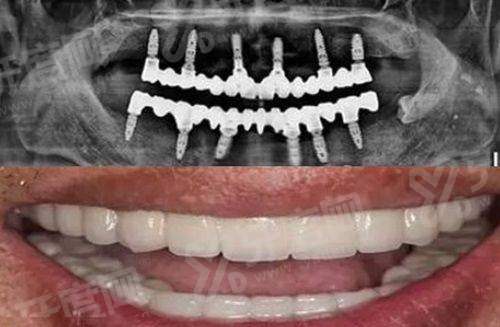

数字化种植技术:采用3D导板精细种植,通过口腔CT扫描获取患者口腔三维数据,术前模拟种植路径,术中精细植入种植体,减少手术创伤,缩短愈合时间,适用于单颗、多颗及半口/全口缺失牙患者。

上海同口名一口腔半口种植牙价格:2.5万元起

上海同口名一口腔全口种植牙价格:4万元起